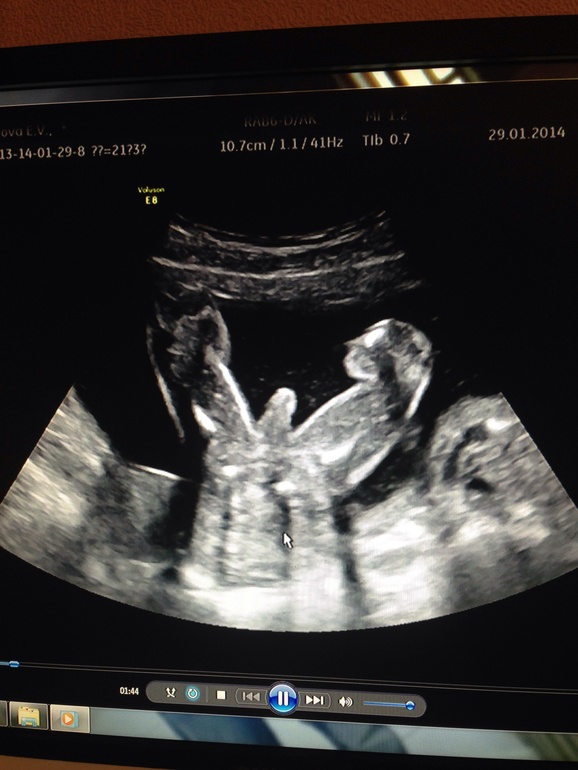

Пузяши наши, ВДМ, тазСходила вчера на повторное узи после курса глюкозы с аскорбинкой из-за взвесей,ситуация не изменилась...ну об этом чуть позже) сначала о сынуле) подросли за 2 недели: 17.01 были 291гр, 29.01 462 гр) пдр сместили на 6.06(было 8.06)т.к. немного вышли вперед акушерского срока, но я как-то не особо равняюсь на узи, в любой момент может сравняться, а может отстать) да и разница малюсенькая) показали нам наше достоинство) сказали ошибки здесь быть точно не может, ну я так, уточнила на всякий случай)))

Вот)))